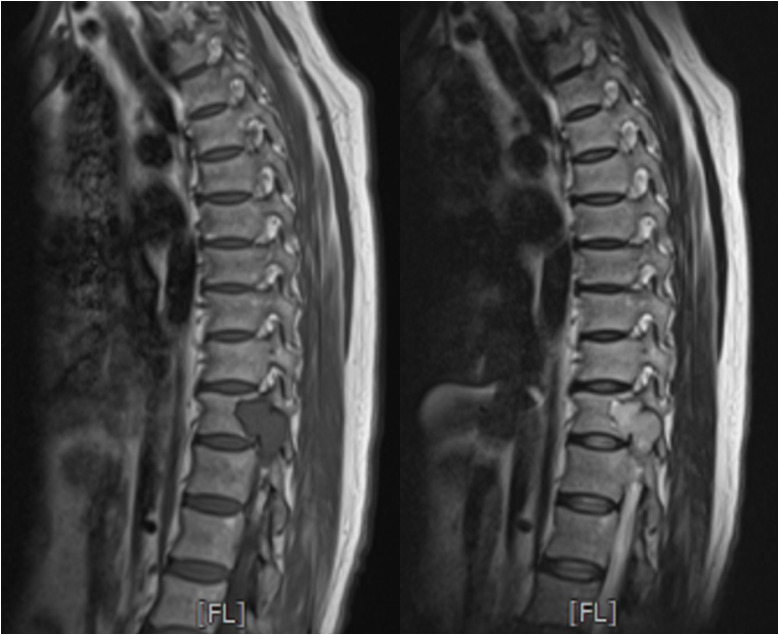

四个月前,这位患者因右侧小腿无力,辗转于西安多家医院寻求治疗,但均未能获得显著改善。随着病情恶化,她的右下肢无力症状逐渐加重,并导致无法行走。患者来到我院骨科中心门诊,秦杰副主任医师接诊后,经过细致的查体,发现患者双侧下肢感觉减退,右下肢的屈髋、伸膝及足背伸跖屈肌力均显著下降(0-1级)。鉴于病情严重,秦杰副主任医师果断将患者收治入院,并进行了详尽的神经系统检查。影像学结果显示,患者胸11-12椎体平面椎管内存在巨大占位,严重压迫脊髓,并已穿过右侧椎间孔向右侧胸腔生长。幸运的是,全身检查并未在其他部位发现原发肿瘤。

明确病情后,与患者家属充分沟通交流了病情,病人椎管内占位体积庞大且生长迅速,若不及时手术挽救残余神经功能,患者将面临双下肢瘫痪,生活质量将急剧降低。然而,手术风险同样巨大,肿瘤不仅巨大且位置深邃,与脊髓关系紧密,椎管侵占率超过了80%以上,稍有不慎便可能损伤脊髓和大血管,危及生命。经过多学科团队协作(MDT)深入讨论和充分的围术期准备,王栋教授带领团队为患者制定了周密的治疗方案。